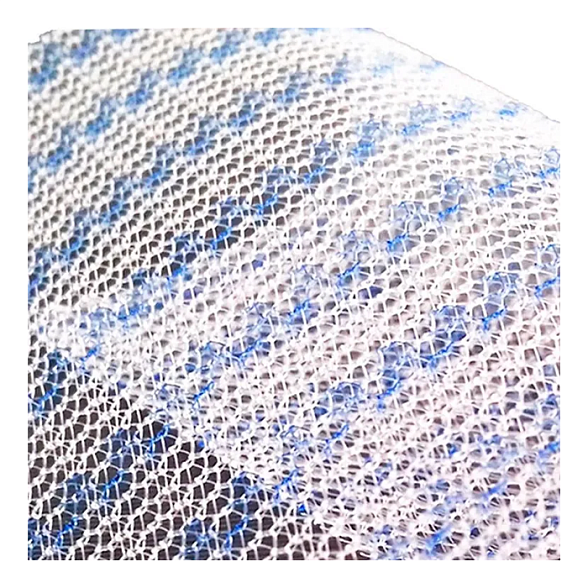

Эндопротез-сетка (сетка хирургическая) полипропиленовый для восстановительной хирургии ЭСФИЛ лёгкий, 30х10 см, Линтекс

Эндопротез-сетка полипропиленовая ЭСФИЛ лёгкий для восстановительной хирургии

Эндопротез-сетка ЭСФИЛ лёгкий от компании «Линтекс» — это современный полипропиленовый имплантат, разработанный для эффективного и надежного восстановления анатомических структур в хирургической практике. Изделие размером 30х10 см представляет собой легкую макропористую сетку, которая служит прочным каркасом для укрепления тканей и стимулирования их естественной регенерации.

Ключевое преимущество сетки ЭСФИЛ лёгкий — её особая конструкция, обеспечивающая высокую биосовместимость и минимальную реакцию со стороны организма. Это позволяет снизить риск послеоперационных осложнений и способствует быстрому восстановлению пациента.

- Минимальная реакция тканей: Макропористая структура и легкий вес материала способствуют быстрому прорастанию соединительной ткани, формируя прочный рубцово-сетчатый комплекс с минимальным риском образования грубых спаек.

- Удобство в работе: Материал легко моделируется и кроится непосредственно в операционной, идеально адаптируясь к анатомическим особенностям пациента. Сетка не скручивается и хорошо держит заданную форму.

| Тип структуры | Макропористая, легкая, не расслаивающаяся |